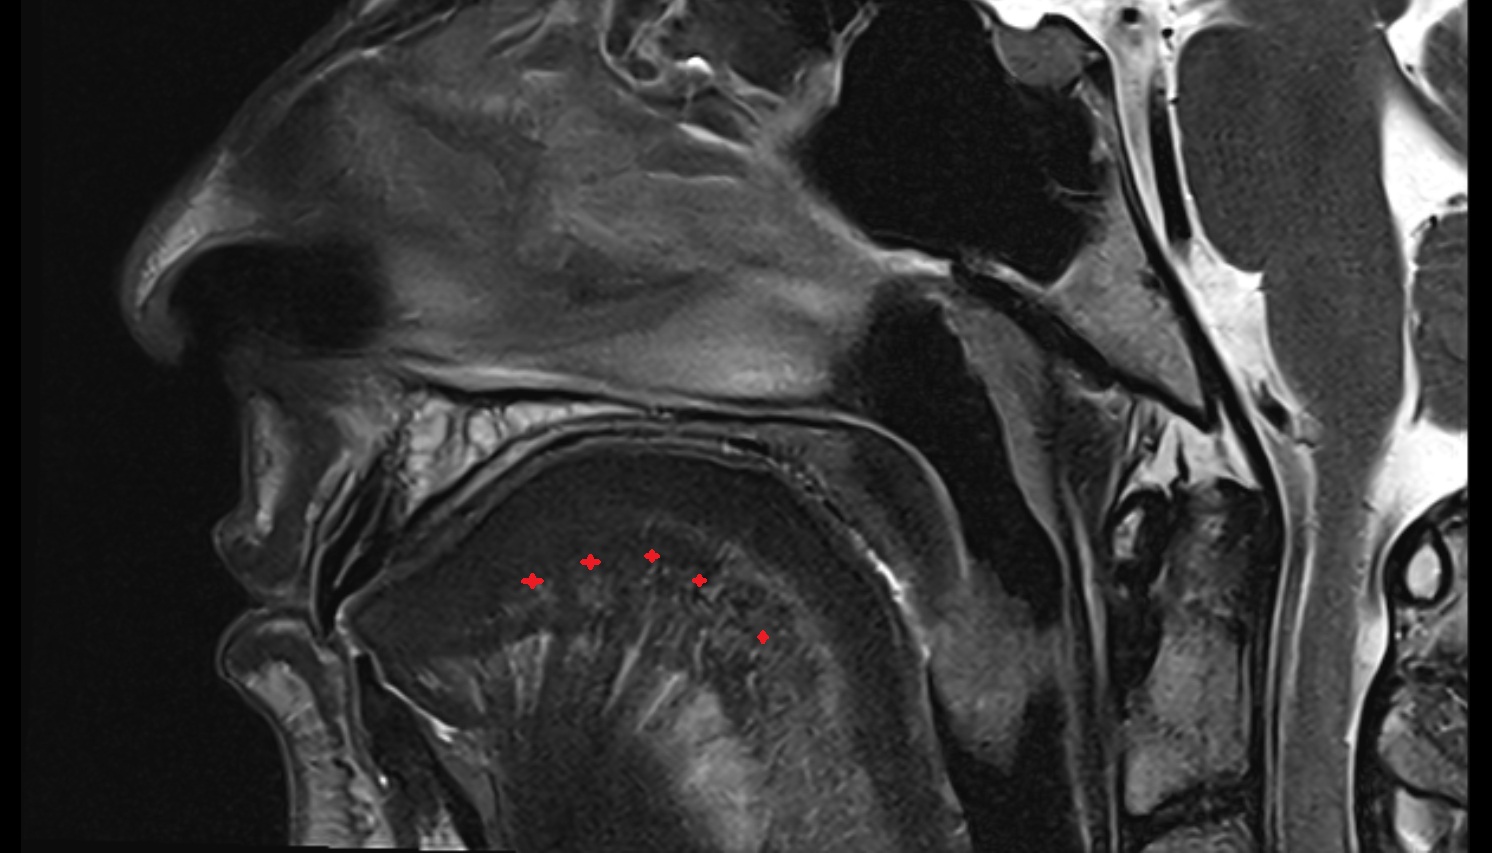

- Hippocampal head

- Head of hippocampus